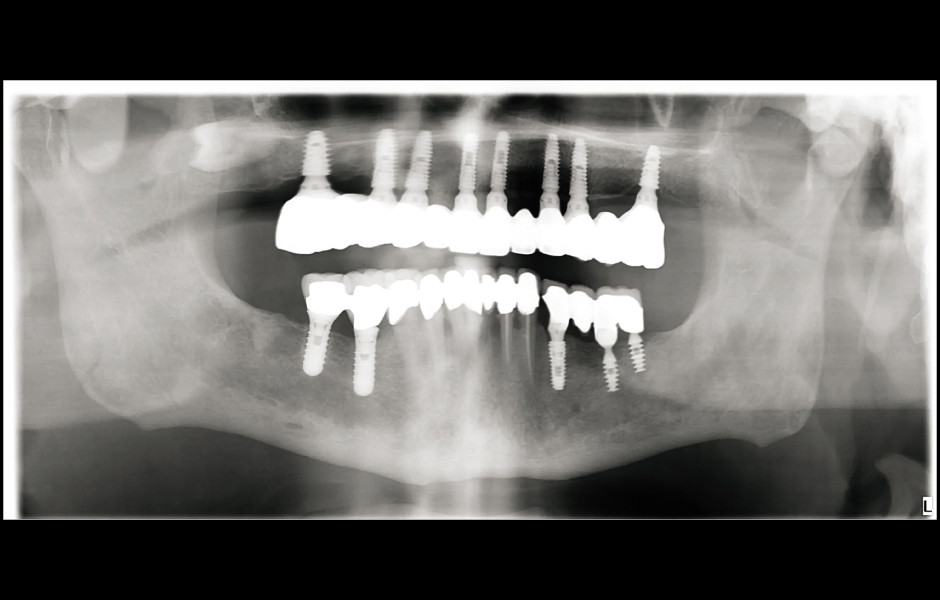

Při finální návštěvě byla nasazena definitivní hybridní šroubem fixovaná protetika. Definitivní práce sestávala z CAD/CAM titanového skeletu přišroubovaného na všechny implantáty a tří monolitických zirkoniových segmentů vlepených nahoře (obr. 18a–c). Byla zkontrolována okluze a pacient byl zařazen do čtyřměsíčního recall programu. Při poslední kontrole (rok po implantaci) byly všechny implantáty úspěšné a pacient byl plně spokojen s novou protetikou (obr. 19–22).

Obr. 22: Panoramatický rentgenový snímek chrupu po jednom roce.